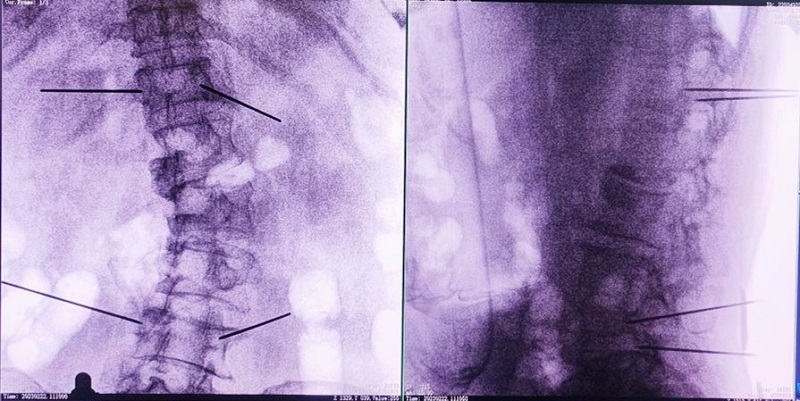

(3)根據設定好的的位置和入針方向,植入引導針;

(4)所有引導針植入完畢后,沿引導針方向進行椎弓根及椎體置管,建立通道;